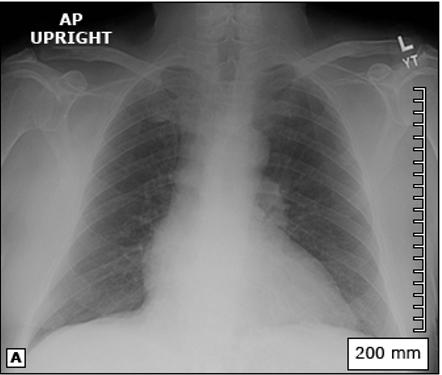

Figura 31. La radiografía de tórax (A) muestra un mediastino ensanchado después de una lesión contusa en el tórax (flechas). Figura 32. El aortograma en proyección anteroposterior (B) muestra un desgarro circunferencial del istmo (flecha). Se observa un pequeño pseudoaneurisma en el sitio de inserción del ligamento arterioso (punta de flecha).

A B